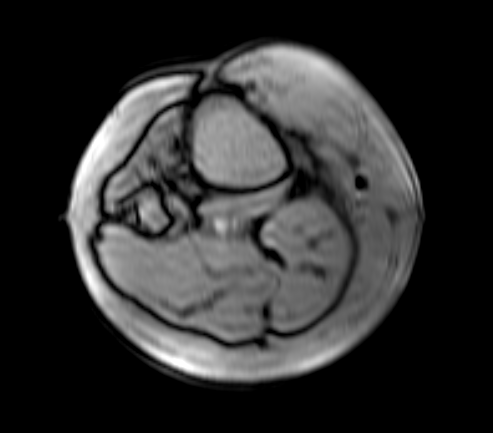

Inverting Image to Greyscale

To toggle an image between positive and negative:

-

Select it in an Image Frame of the Series View

-

Click the Invert greyscale icon

on the toolbar

on the toolbar

Positive Negative